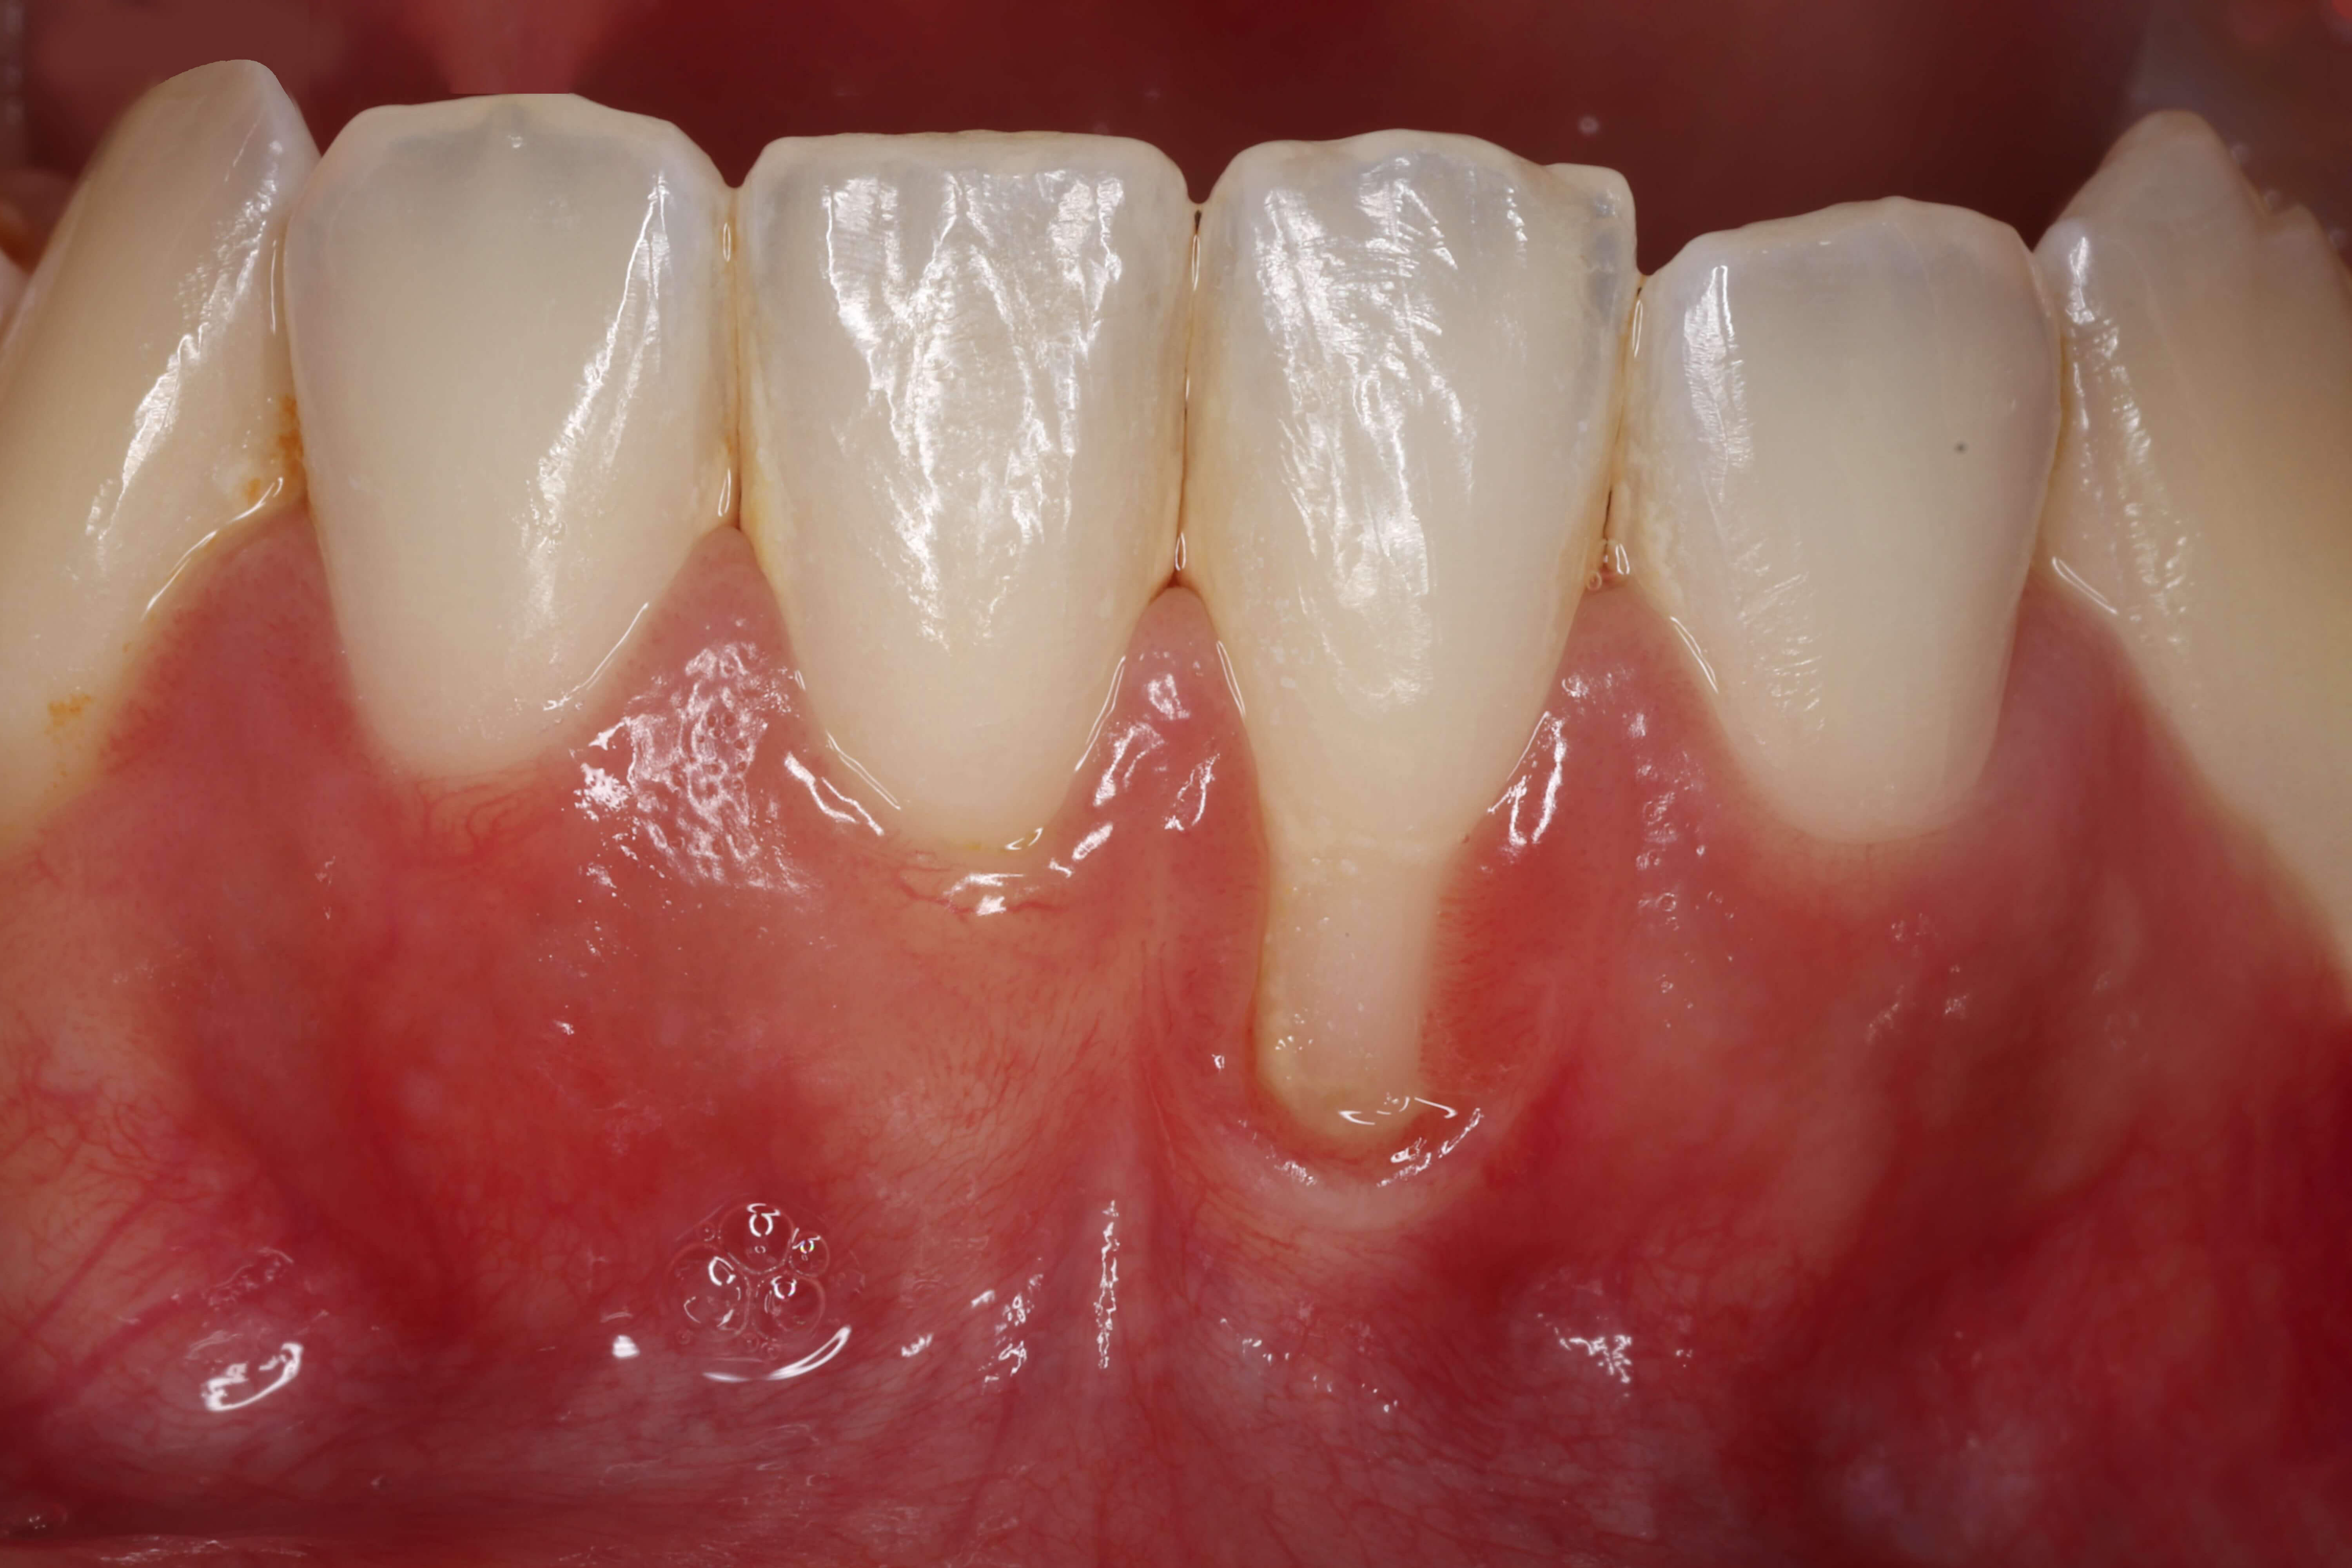

Caso clínico do Dr.º Tiago Rodrigues

A inflamação gengival ocorre devido à acumulação de placa bacteriana e tártaro junto da margem da gengiva. A fase inicial da doença é designada por gengivite e é caracterizada por: sangramento gengival, inchaço da gengiva, mau cheiro e por vezes desconforto ao toque. A gengivite tem uma resolução muito fácil e é completamente reversível. Na ausência de tratamento, a gengivite pode evoluir para periodontite, verificando-se adicionalmente: reabsorção óssea, recessão gengival, mobilidade dentária e eventualmente perda dos dentes. A periodontite quando não tratada é uma das principais causas de perda dentária nos adultos.